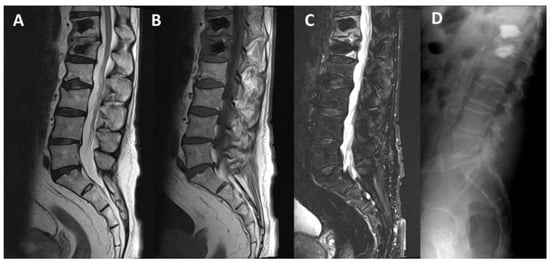

- Pusceddu, C.; Marsico, S.; Derudas, D.; Ballicu, N.; Melis, L.; Zedda, S.; de Felice, C.; Calabrese, A.; De Francesco, D.; Venturini, M.; et al. Percutaneous Vertebral Reconstruction (PVR) Technique of Pathological Compression Fractures: An Innovative Combined Treatment of Microwave Ablation, Bilateral Expandable Titanium SpineJack Implants Followed by Vertebroplasty. J. Clin. Med. 2023, 12, 4178. [Google Scholar] [CrossRef]